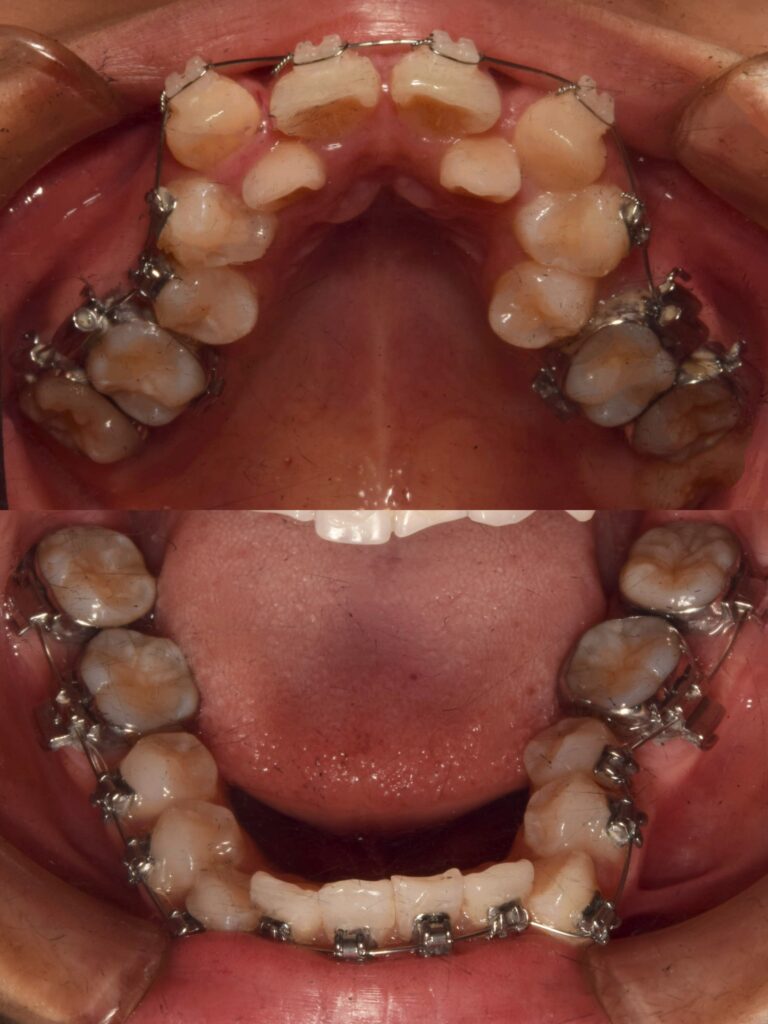

今回のリールでは、矯正治療のビフォーアフターを載せています💫

かなりガタガタだった歯並びでも、矯正治療できちんとここまでキレイに整います✨✨